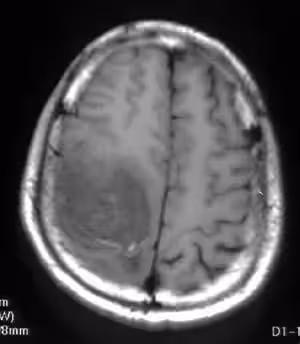

一次例行健康檢查後,醫生告訴何阿嬤,原來,這個寶寶患有重度身心障礙,除腦水腫外,還患有癲癇、過動、斜視等問題。

拿到殘障手冊當天,她抱著明琴崩潰大哭了很久。